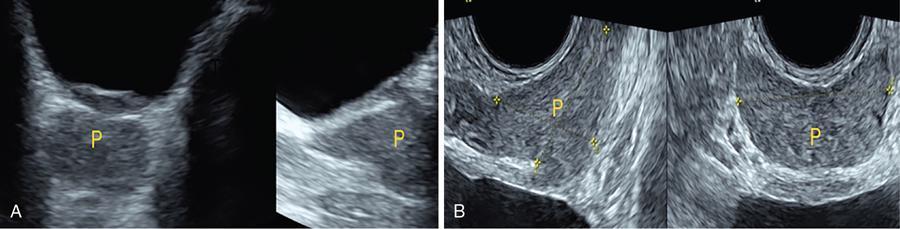

IMAGING ANATOMY OF MALE REPRODUCTIVE SYSTEM Ganesh Rajagopal The male reproductive system is formed by testes, ejaculatory ducts, seminal vesicles (SVs), prostate and penis. Various diagnostic imaging modalities like ultrasound (US), computed tomography (CT), magnetic resonance imaging (MRI) and positron emission tomography (PET) are helpful in the diagnostic evaluation of male reproductive system. Various indications for imaging may include acute scrotum (testicular torsion, trauma and epididymo-orchitis), scrotal swelling (hydrocele, spermatocele, idiopathic scrotal wall oedema and scrotal abscess) and infertility. US and MRI are the commonly used imaging modalities in male reproductive system which complement each other. CT is not very useful due to poor contrast resolution. Ultrasound imaging (US) with a high-frequency linear (7.5–10 MHz) transducer probe has become the imaging modality of choice for scrotal evaluation. Scrotal US is an excellent imaging modality as it can demonstrate abnormalities in testis as well as in paratesticular structures. Scrotal wall is formed by the skin, superficial fascia, dartos muscle, the external spermatic fascia, cremasteric fascia and the internal spermatic fascia. The scrotum is divided into two cavities by a median raphe. This multilayered scrotal wall is poorly delineated in US and MRI, it is typically hypointense on both T1- and T2-weighted images. Testes are paired organs, located normally in scrotal sac, suspended by the spermatic cords. Each testis is examined in orthogonal transverse and longitudinal planes, with both grey scale and colour Doppler modes, to assess its volume and blood flow. Volume of testis is calculated by length × height × width × 0.71. A total volume (both testes) of >30 mL and a single testicular volume of 12–15 mL is generally considered normal for adults. Testes are supplied by the testicular arteries, which arise from the aorta and enter the spermatic cord at deep inguinal ring to reach the upper pole of testis. Pampiniform plexus of veins surrounds the testis and appears as a serpiginous tubular structure posterior to it, measuring >2–3 mm in diameter. Testes are oval shaped, with homogeneous echotexture on grey scale US. Along with the epididymis, they are surrounded by an echogenic capsule, known as the tunica albuginea. Tunica albuginea is covered by tunica vaginalis, which is a remnant of the processus vaginalis and both represent closed sac of peritoneum with two layers. This tunica albuginea is seen extending into posteromedial testis and form the mediastinum testis (Fig. 11.2.1.1), which consists of ducts, nerves and blood vessels. The mediastinum testis is seen as a thin echogenic band. Rete testis is formed by the convergence of seminiferous tubules, seen as a hypoechoic area adjacent to mediastinum testes. The epididymis is a comma-shaped, elongated structure placed at the posterior border of the testis, which drains the efferent ductules (Fig. 11.2.1.2). It has head, body and tail. The head overlies the superior pole of the testis and is isoechoic or slightly hyperechoic whereas, the body and tail are located behind and along the inferior pole and are usually isoechoic. The tail of the epididymis continues into vas deferens (VD), which along with the nerves, lymphatic and vascular structures, forms the spermatic cord (Fig. 11.2.1.3). The spermatic cord appears as an echogenic band in the inguinal canal. The normal adult testis is a homogeneous oval structure that appears hyperintense on T2-weighted sequences and hypointense–isointense on T1-weighted images (Fig. 11.2.1.4). The tunica which surrounds the testis is hypointense T1- and T2-weighted sequences. Epididymis is isointense on T1-weighted images but hypointense on T2-weighted images compared to testis (Fig. 11.2.1.5). Both testicles and epididymis enhance after intravenous administration of gadolinium (Gd) MR contrast agents. Prostate, though visualized by transabdominal scan is better assessed by transrectal high frequency (7.5–10 MHz) ultrasound transducer (TRUS) with patient in left lateral decubitus position. The prostate gland is divided into the anterior fibromuscular stroma (devoid of glandular tissue), transition zone, central zone, periurethral zone and peripheral zone. The base of the prostate is located superiorly and contiguous with the bladder neck whereas, the apex of the prostate is located at the inferior aspect continuous with the striated muscles of the urethral sphincter. The neurovascular bundle is seen to course near the posterolateral aspect of prostate, which is a preferential route of tumour spread. The prostate appears as a cone-shaped organ and shows uniform low echogenicity (Fig. 11.2.1.6). The outer gland (central and peripheral zones) is generally more echogenic than the inner gland. The transition and central zones of the prostate have similar MR signal intensity and cannot be differentiated, hence, are collectively referred as the central gland. On T2-weighted MR images, the normal peripheral zone is homogeneously hyperintense, whereas the central gland tissue is typically hypointense or isointense compared to the skeletal muscle (Fig. 11.2.1.7). The capsule and the anterior fibromuscular stroma appear hypointense on T2-weighted MR images. The SVs are seen as septate tubular cystic structures, appearing uniformly anechoic in US, above the prostate with distal portion of VD is seen medial to it. The duct of SV and VD joins to form the ejaculatory duct, which drains into the prostatic urethra via verumontanum. SVs show ‘bow-tie’ appearance in transversal scans, and a club or tennis-racket shape in longitudinal scans (Fig. 11.2.1.8). On MR, SVs are seen as elongated fluid-containing structures with thin septa, which is hypointense on T1 and hyperintense on T2-weighted MR images (Fig. 11.2.1.9). The VD is seen as a tubular structure with low signal intensity in both T1- and T2-weighted images, on either side. The dilated distal portion of VD (ampulla), appears hyperintense on T2-weighted images, similar to that of the SV due to the fluid content (Fig. 11.2.1.10). The penis, being a superficial organ, is usually examined with US, although MRI is reserved as problem solving modality. The penile body contains two paired muscles – corpora cavernosa and a corpus spongiosum. The former performs as a main erectile body while the latter contains the penile urethra (Fig. 11.2.1.11). Dartos fascia forms the outer layer and the Buck fascia forms the inner layer, which contain the deep dorsal vein (DDV) and a paired dorsal neurovascular bundle. The corpus spongiosum and corpora cavernosa are of high signal intensities on T2-weighted MR images and intermediate-low signals on T1-weighted MR images. The tunica albuginea being a fibrous sheath, surrounds all the three muscles, is hypointense on all sequences (Fig. 11.2.1.12). IMAGING ANATOMY OF FEMALE REPRODUCTIVE SYSTEM Saranya The female reproductive system comprises of uterus, cervix, fallopian tubes, ovaries, vagina and vulva. Ultrasonography (transabdominal and transvaginal) is the primary imaging modality of choice for imaging the female pelvis. Computed tomography (CT) is less often used for pelvic imaging. It provides a quick and systematic overview with coverage of the abdomen in the same session. Hence, CT is well suited for staging pelvic cancers and for imaging gynaecologic and nongynaecologic diseases presenting with acute abdominal pain. Pelvic anatomy is well demonstrated by magnetic resonance imaging (MRI). The contrast resolution of T2-weighted images form the basis for superb tissue characterization of MRI. Uterus is a thick-walled fibromuscular organ composed of myometrium and endometrium. It has two major divisions, namely, the body (corpus) and cervix. The fundus lies above the ostia of fallopian tubes. The normal uterus measures between 5 and 9 cm in length and is in an anteverted position, in relation to the urinary bladder. The myometrium shows three layers on USG, a compacted thin, hypoechoic inner layer forms subendometrial halo, a thicker, homogenously echogenic middle layer and a thinner, hypoechoic outer layer (peripheral to arcuate vessels). The appearance of the endometrium varies with the phase of the menstrual cycle. It appears as a thin echogenic line early in the proliferative phase and shows hypoechoic thickening (4–8 mm) as proliferative phase progresses. It shows a triple layer (sandwich or trilaminar) appearance in the mid cycle and may measure up to 12–16 mm. During secretory phase after ovulation, the layers are seen hyperechoic due to the increasing complexity of glandular structure and secretions (Fig. 11.2.2.1). Postmenopausally, the endometrium decreases in thickness. Endometrial thickness of 5 mm is taken as cut-off. Women on hormonal therapy acceptable endometrial thickness is up to 8 mm. Three-dimensional US permits multiple views to be reconstructed from a single sweep through the uterus. Sonohysterogram is the study of choice for detailed evaluation of the endometrial cavity pathologies. The cervix begins at the inferior narrowing of the uterus (isthmus) at the internal os, which is identified by the entrance of uterine vessels. It has supravaginal and vaginal portions. It is 3–4 cm long and shortens after childbirth. In premenarche women, cervix is larger than corpus, forming approximately 2/3 of the uterine mass. During menarche, there is preferential growth of the corpus and in nulliparous women, corpus and cervix are roughly equal, whereas in parous woman, corpus forms approximately 2/3 of the uterine mass. Uterus is an extraperitoneal organ. The peritoneum extends over urinary bladder dome to anterior uterus, forming anterior cul-de-sac (vesicouterine pouch) and posteriorly, the peritoneum extends more inferiorly to the upper portion of vagina, forming the posterior cul-de-sac (pouch of Douglas, rectouterine pouch), which forms the most dependent portion of the female pelvis. Supporting ligaments of the uterus comprise mainly of broad ligaments, which extend laterally to the pelvic wall and round ligaments, which arise from uterine cornu near fallopian tubes to course anteriorly, pass through the inguinal canal to insert on the labia majora. Connective tissue thickening at the base of the broad ligament forms the uterosacral ligaments posteriorly, cardinal ligaments laterally and vesicouterine ligaments anteriorly. CT examination displays the uterus as a triangular or ovoid soft tissue structure behind the urinary bladder (Fig. 11.2.2.2). Following the administration of intravenous contrast, there is enhancement of myometrium that helps to delineate the endometrium. The vagina, cervix and corpus can be differentiated by morphological characteristics and enhancement pattern. The uterine corpus is typically triangular, whereas cervix is more rounded. The vagina has an appearance of flat rectangle at the level of fornix. The broad ligament and round ligaments are seen coursing laterally and anteriorly, respectively. The main source of vascular supply to uterus is from the uterine arteries. The uterine arteries pass within the broad ligament to enter the uterus, adjacent to the lateral fornices. The uterine artery passes over the ureter at the level of the cervix. Then it courses superiorly, along the lateral margin of the uterus and anastomoses with the ovarian artery. Uterine arteries give rise to arcuate arteries, which run in the outer third of myometrium. Radial arteries extend through the myometrium, which terminate as spiral arteries in the endometrium. The venous system parallels the arterial system, forms a complex venous network in the parametrium and drains to the iliac veins. Middle and lower thirds of the uterus are drained by obturator, parametrial and paracervical lymph nodes. Lymphatic drainage from the upper corpus and fundus goes to the common iliac and paraaortic lymph nodes. MRI provides a more comprehensive view of the uterine anatomy. On MRI, the uterus and cervix show uniform low to intermediate signal on T1-weighted images. On T2-weighted images, uterus shows three distinct zones, namely high signal endometrium, low signal junctional zone and intermediate signal myometrium (Fig. 11.2.2.3). The normal thickness of the junctional zone varies from 2 to 8 mm. A thickness of 9 to 12 mm is equivocal and greater than 12 mm is abnormal. Both endometrium and junctional zone become thin with oral contraceptive intake. Endometrial atrophies and the junctional zone is absent in postmenopausal women. The endocervical canal shows high signal on T2-weighted images, whereas cervical stroma shows low signal, contiguous with the junctional zone. An outer layer of intermediate signal smooth muscle is present. Nabothian cysts representing obstructed, mucous secreting glands are commonly seen as low signal on T1-weighted images and high signal on T2-weighted images. Parametrium shows low to intermediate signal intensity on T1-weighted images and variable signal intensity on T2-weighted images. The round ligaments and uterosacral ligaments show low signal intensity, cardinal ligaments and associated venous plexuses show high signal intensity on T2-weighted images. Ovaries are located posterolateral to the body of the uterus between the uterus and the pelvic sidewall. The internal iliac vessels lie immediately posterior to the ovary. Exact position is variable due to the laxity in the ligaments, parity, uterine size and position. On USG, medulla of the ovaries is mildly hyperechoic compared to the hypoechoic cortex. Developing follicles appear anechoic (Fig. 11.2.2.4). Corpus luteum may have a thick, echogenic ring and haemorrhage is common.